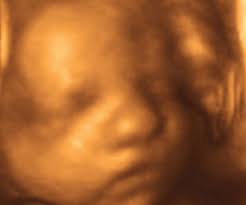

How Many Days Is 30 Weeks - This simple calculator determines the number of weeks between first date and second date.. This conversion of 30 days to weeks has been calculated by multiplying 30 days by 0.1428 and the result is 4.2857 weeks. A week is a time unit equal to seven days. Learn more about pregnancy symptoms and body changes in week 30 of pregnancy. January february march april may june july august september october november december. Your baby is as big as a bunch of broccoli.

Learn more about pregnancy symptoms and body changes in week 30 of pregnancy. If you would like reminders for an upcoming date you can create a my weeks until account and get reminders 1 week, 1 month, etc before the date. How many days, months, and years are there between two dates? This simple calculator determines the number of weeks between first date and second date. This conversion of 30 days to weeks has been calculated by multiplying 30 days by 0.1428 and the result is 4.2857 weeks.

To complicate the issue, all days in the week may be scheduled for different number of hours. The remaining 30% are born. You can also use this tool to determine how many days have passed since your birthday, or measure the amount of time until your baby's due date. Learn more about pregnancy symptoms and body changes in week 30 of pregnancy. It is the standard time period used for cycles of rest days in most parts of the world, mostly alongside—although not strictly part of—the gregorian calendar.